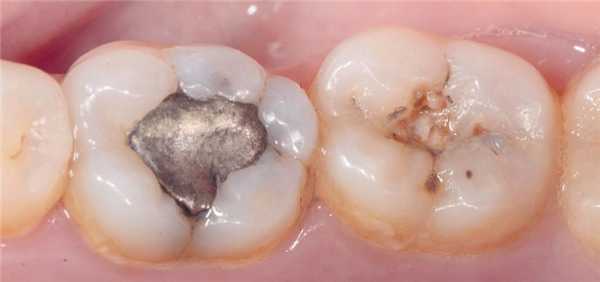

Фото 4. Дефектная реставрация в двух нижних молярах.

Фото 5а и 5с. Восстановление дентина порцией материала Tetric EvoFlow Bulk Fill. Благодаря технологии Aessencio опаковость материала увеличивается в ходе полимеризации.

Клинический случай 1

35-летняя пациентка обратилась за стоматологической помощью с просьбой заменить амальгамные реставрации в области первого и второго нижних молярах. Она также сообщала о наличие болезненных ощущений в проекции данных зубов при жевании. В ходе клинического осмотра были идентифицированы реставрации моляров, требующие срочной замены (фото 4). После удаления старых пломб и нанесения универсального адгезива Adhese Universal, объем дентина был восстановлен материалом Tetric EvoFlow Bulk Fill (фото 5). Данный композит обладает очень хорошими свойствами самовыравнивания и автоматически принимает вогнутую форму. В области второго моляра текучий композит вносили одновременно и на окклюзионную и на контактную поверхности. Полимеризацию обеспечивали лампой Bluephase (1200 мВт/см2) в течение 20 секунд. Производитель рекомендует обеспечивать полимеризацию композита на протяжении 10 секунд. Внесенная толщина слоя текучего композита не превышала 4 мм. Благодаря технологии Aessencio опаковость материала значительно увеличивается в процессе полимеризации (фото 5). Эмаль восстанавливали посредством материала Tetric EvoCeram A3, используя технику последовательного наращивания бугров. Фиссуры окрашивали при помощи IPS Empress Direct Color Brown (фото 6). Корректировку окклюзионных соотношений проводили после удаления коффердама. Поскольку бугорки изначально были смоделированы правильно, требовалась лишь минимальная окклюзионная коррекция, после которой приступили к полировке реставрации системой Astropol. Поверхности реставраций плавно сливались с окружающей структурой зуба (фото 7).